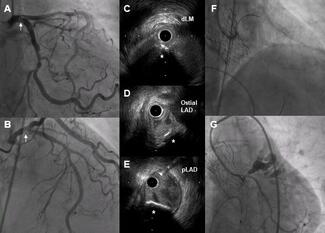

A 77-year-old woman with hypertension and diabetes presented with exertional angina and dyspnea. Subsequent workup showed severe aortic stenosis and severe calcified stenosis at the proximal left anterior descending artery.